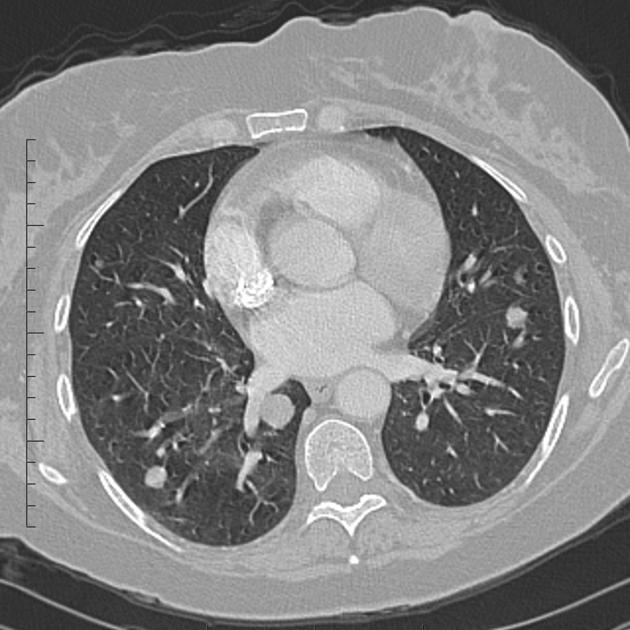

- 흉부 CT: 폐 전이를 가장 정확하게 확인할 수 있는 검사